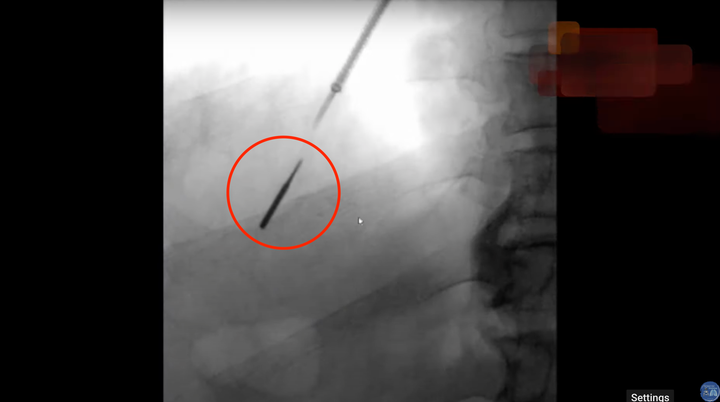

The bit embedded itself so deeply in Jozsi’s lung that conventional tools couldn’t reach it, forcing interventional pulmonologist Dr. Abdul Alraiyes to take a more creative approach.

Wielding a tiny robotic bronchoscope typically reserved for sampling suspicious tissue deep in the lung, Alraiyes was able to ever-so-carefully extract the bit. The operation, carried out at the Aurora Medical Center in Kenosha, Wisconsin, was a success.

Video of the procedure uploaded to Alraiyes’ YouTube channel resembles a high-stakes version of the claw machine so often attempted and failed by children at vending machines everywhere.